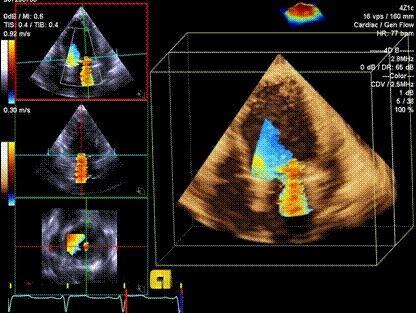

运动负荷超声心动图

运动负荷超声心动图,

平板运动超声心动图舒张负荷试验的预后价值

三维超声心动图显示左室侧壁无运动

超声心动图